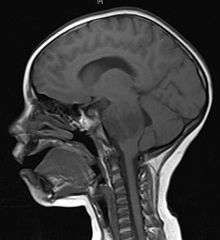

A brainstem glioma in four-year-old. MRI, sagittal, without contrast